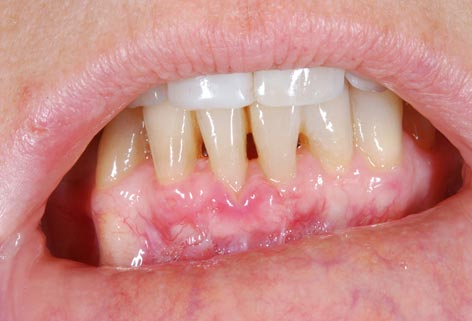

Lembo libero per correggere una recessione gengivale